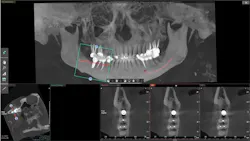

- Radiographs: Panoramic radiographs a monitor directly in front of the patient when they enter the operatory can be one of the most important educational tools. Patients can see what you are discussing and better understand what treatment you are proposing for them (figure 1). Cone beam radiographs are excellent educational images especially when discussing implants, showing bone quantity and quality, as well as vital structures (figure 2). Periapical and bitewing digital radiographs show some carious lesions, but need more definition than they currently provide.